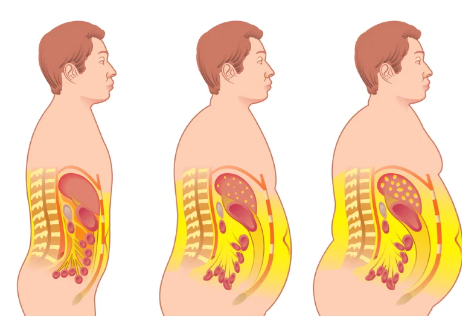

Perut Buncit = Visceral Fat = Sumbatan Lemak Berlebih!

Dr. Yosua : Pertama, Anda harus tahu, bahwa semakin buncit perut Anda, Anda akan mengalami yang namanya penambahan lemak viseral (visceral fat). Fungsi lemak viseral dalam tubuh kita itu melindungi organ vital pada bagian perut. Tapi, yang jadi masalah ketika jumlahnya terlalu banyak, maka Anda akan melihat gambaran organ yang sulit bekerja akibat tertutup lemak ini.

Kinerja otot jantung akan semakin berat dan salah satu resiko paling buruk adalah serangan jantung! Ini baru efek pertama, belum lagi jika kita bahas, LDL yang menghambat pembuluh darah di jantung. Kemudian aterosklerosis (penyempitan dan pengerasan pembuluh darah arteri akibat penumpukan plak di dinding pembuluh darah) yang tentunya berdampak kepada naiknya tekanan darah (hipertensi), seperti yang dialami oleh Pak Mahfud tadi. Hipertensi yang dibiarkan adalah pemicu serangan stroke. Karenanya, Anda sama sekali tidak bisa memandang remeh.